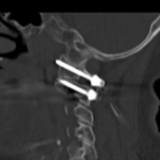

术中,在麻醉科与手术室护理团队的紧密配合下,脊柱外科手术团队充分发挥扎实的解剖知识、精湛的操作技术与丰富的临床经验,在狭小的手术空间内展开精准操作。脊柱手术中螺钉置入的难度极高,素有“螺蛳壳里做道场”“针尖上跳舞”之称,每毫米的进钉偏差,都可能直接影响手术成败,甚至威胁患者安危。最终,手术团队成功避开重要神经血管,将多枚内固定螺钉精准植入预定位置。术后透视结果显示,患者骨折复位效果理想,内固定位置精准无误,手术圆满完成。